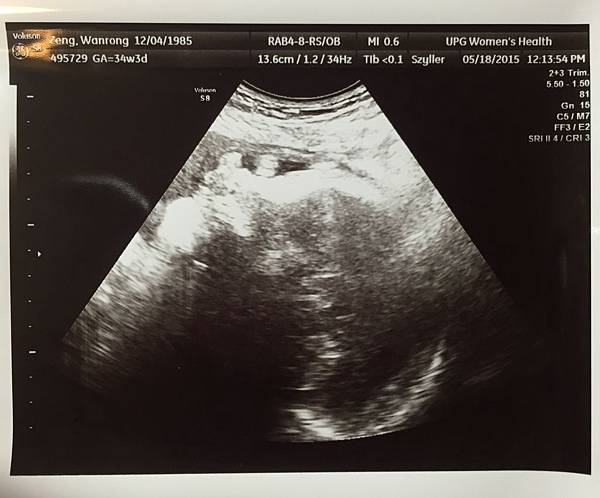

答案揭曉......2211g!!

低於50%標準值一點 但還在正常範圍

這標準值好像是美國寶寶的標準 呵

醫生說頭圍、腹圍、大腿骨長度都不錯

也看了Elvia的位置

她頭在下面 右側睡

胎盤位置一樣在前面 偏上面

附上珍貴的超音波側臉照 臉上是肥肥的小手 好可愛